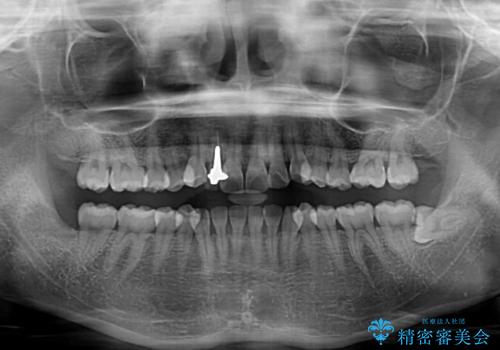

- 上下前歯のデコボコを気にして来院された患者様です。

インビザラインによる上下歯列の拡大と、IPR(歯と歯の間を削る)にるスペースの獲得により、前歯のデコボコを改善することとしました。

下顎前歯は後戻りを起こしやすいため、舌側を細いワイヤーで固定し、マウスピース型リテーナーで保定を行うこととしました。